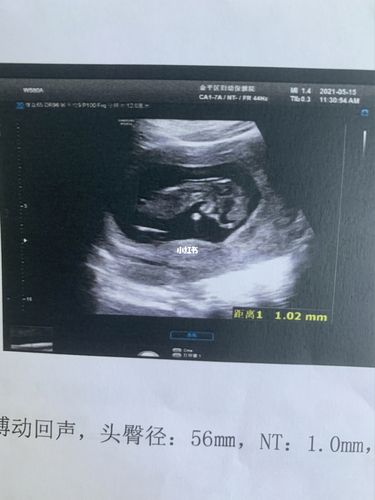

nt宝宝坐着的图片,12周nt宝宝图片

12周nt宝宝图片

孕12周做nt的图片

nt检查图片